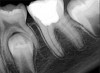

Fig 15. Preoperative radiograph. Courtesy of Dr. Sam Kratchman.

Figure 15

Fig 16. Post apicoectomy. Courtesy of Dr. Sam Kratchman.

Figure 16

Case 3: Apicoectomy and Retrofill

A patient presented with clinical symptoms and radiographic signs of post-endodontic disease (Figure 15). It was determined that the ledge on the mesial canals precluded retreatment and that an apicoectomy was to be performed. After locating the apicoectomy, it was possible to visualize both canals and an obvious isthmus between the two main canals (Figure 16). Retro-preparations were performed in the main canals, and the isthmus between them was grooved and the cavities filled with BC RRM-Putty (Figure 17). At the 20-month follow-up, the patient was asymptomatic and the radiograph showed complete healing (Figure 18).